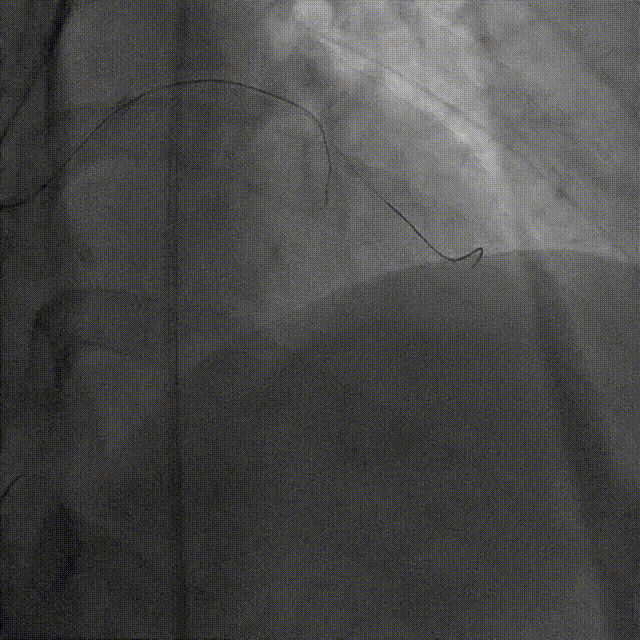

微导管高选择性造影(tip injection)显示远端心外膜侧枝迂曲

Caravel微导管支撑下,SUOH 03导丝通过心外膜侧枝送至LAD闭塞段远端